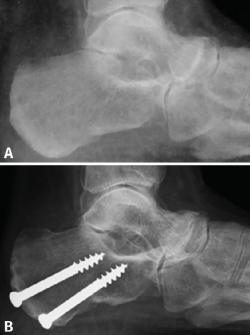

Figura 3. Los cambios radiológicos en la proyección lateral del pie son evidentes después de la cirugía valguizante del retropié. A: artropatía talonavicular en el preoperatorio; B: un año después de la cirugía la articulación muestra un aspecto mejorado por la traslación medial del astrágalo.

Atendiendo a la clasificación radiológica de Maceira(3), en el preoperatorio encontramos 7 pies (41,2%) en un estadio II, 5 (29,4%) en un estadio III y 5 (29,4%) en un estadio IV. A los 12 meses de la cirugía, se observaron cambios notables en la mayoría de los pacientes, destacando la mejora del aspecto de la artrosis y de la cobertura talonavicular. Tras la cirugía se produjo una regresión en los estadios de Maceira, pasando a tener 6 pies con estadio I (35,3%, ninguno preoperatoriamente), 10 pies con estadio II (58,9%, 7 antes de la cirugía), ningún pie en estadio III (5 antes de la osteotomía) y solo en 1 pie persistió el estadio IV (5,9%, 5 en el preoperatorio) (Figura 3). La mejora de la cobertura talonavicular fue significativa, pasando de una media preoperatoria de − 25,35 (− 17 a − 31) a una postoperatoria de − 15,53 (− 9 a − 26) (Figura 4).